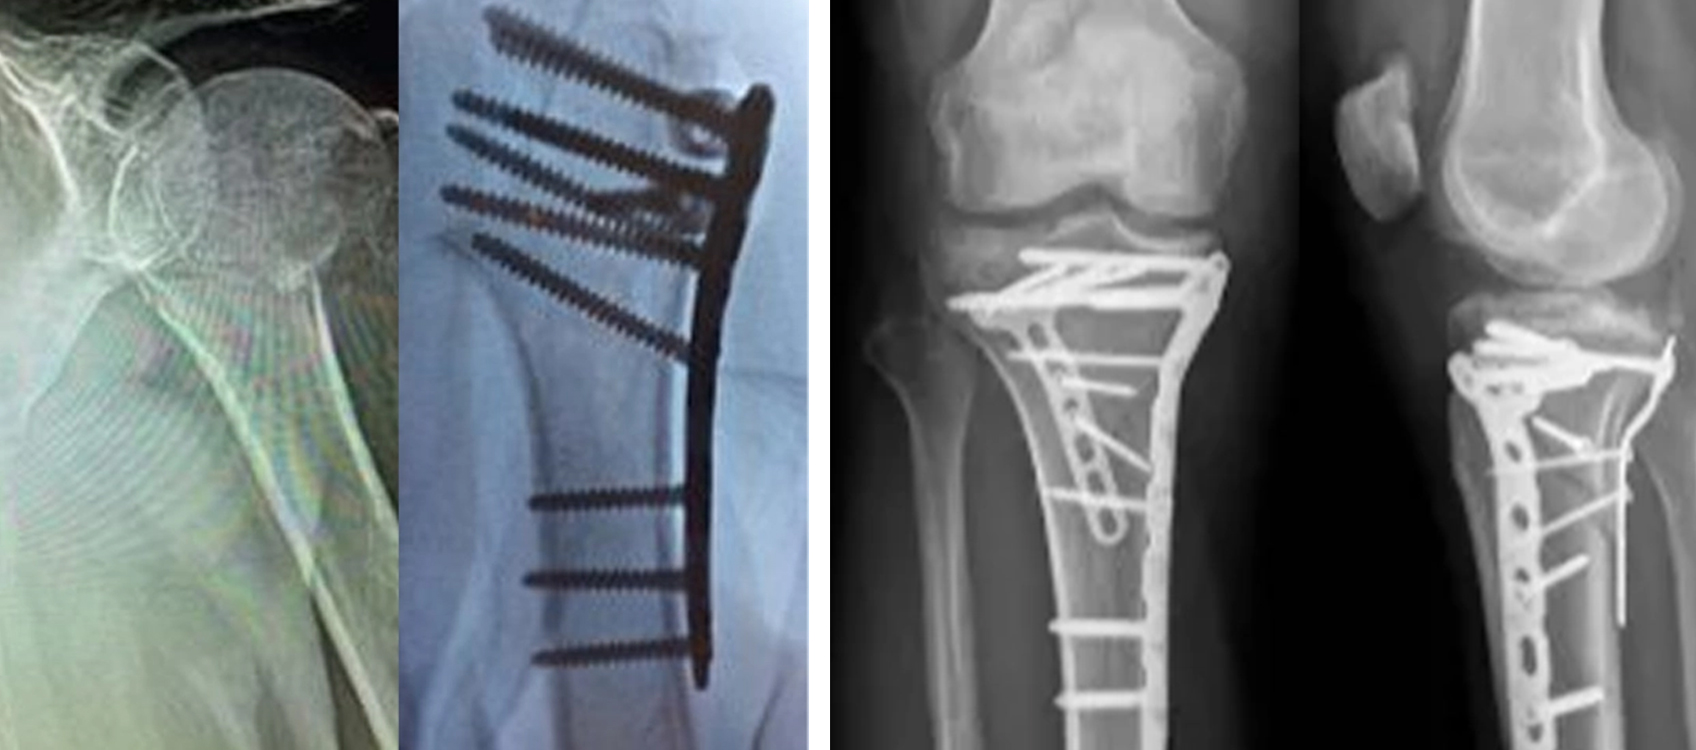

Locking Plate Fixation (ORIF)

Beskoattelje plaatfixaasje wurdt in protte brûkt foar proximale humerusfraktueren, benammen yn osteoporotyske bonken. It soarget foar hoekstabiliteit en makket iere mobilisaasje mooglik.

proximal humerus locking plaat fixation sjirurgyske application.jpg

Foardielen fan Locking Plate Systems

• Hege stabiliteit fixation

• Geskikt foar osteoporotyske bonken

• Multi-angle screw design

• Unterstützt betide rehabilitaasje